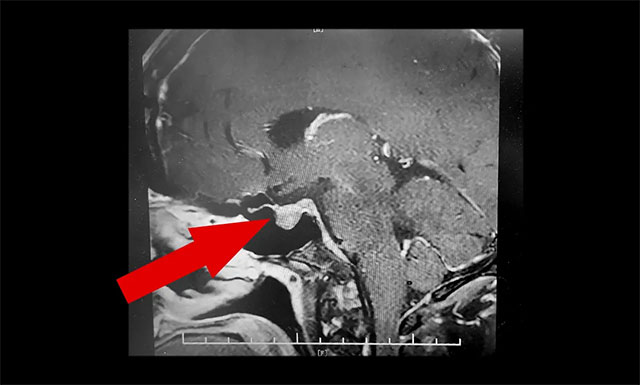

鞍区MRI增强提示:垂体左侧叶占位。检查生长激素5ug/L,远超正常值。入院查体可见口腔黏膜、口唇、鼻粘膜等过度发育增厚,皮肤粗糙,双手、双足肥大。结合病史、影像等,神经外科6B病区潘仁龙主任、李士其教授、吴治群博士会诊后考虑为生长激素垂体腺瘤,该肿瘤约红枣大小,而成人正常的脑垂体不过豌豆大小。正是垂体瘤导致老李面容改变、肢端粗大等。手术指征明确,应尽快手术治疗。

▲ 垂体左侧叶占位,考虑为生长激素垂体腺瘤